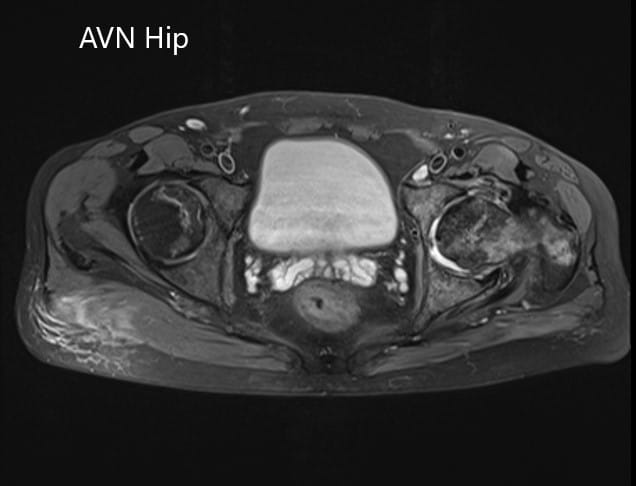

An MRI of the pelvis was obtained which suggested decreased signal intensity on both T1WI and T2WI suggesting sclerosis and periarticular edema. There was a collapse of the head of the femur. The features were suggestive of advanced avascular necrosis of the left hip joint.

Axial section of the T2WI of the pelvis.